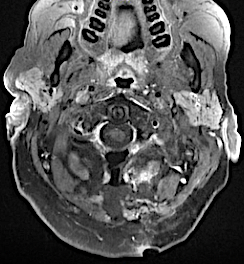

Corte axial C2

Imagen especular: en la derecha se ha marcado en rojo los schwannomas y en amarillo la médula. Se aprecian las raíces C2 engrosadas.